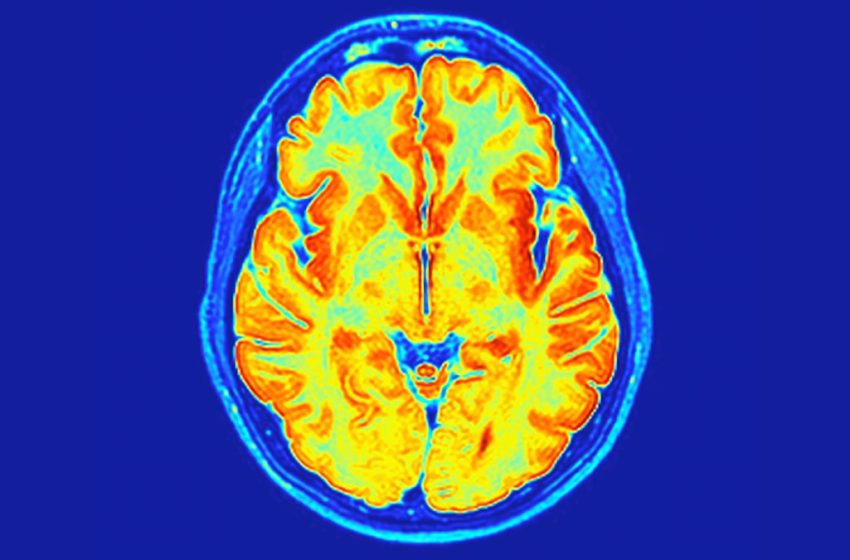

The researchers identified brain structure changes associated with the syndrome. (Greene et al., Nat. Genet., 2026)